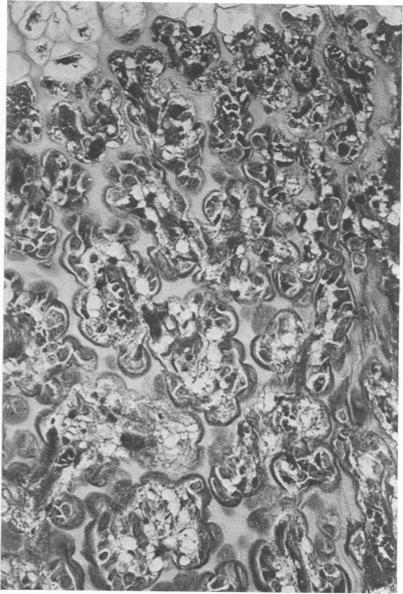

Disease in a large pig herd reared intensively and kept on sulfate-rich drinking water is described. It is the first report of diseased progeny of sows with high sulfate intake. Results of two surveys are presented, one for water with sulfate in excess of 2000 ppm and one for water with less than 1000 ppm. The management practices are described in detail. Disease of Survey I was manifested by high morbidity and mortality (50% of 600) in piglets, incoordination in piglets and some adult stock and osteopathy in piglets and weaners. In Survey II disease was less severe and restricted to piglets. Detailed histopathological studies revealed myelin deficiency in brain and spinal cord of sows and piglets, interferred endochondreal ossification of long bones of piglets and weaners, fatty changes of livers and interstitial nephritis in piglets and weaners. The changes in the nervous tissue were considered due to delayed fixation as tissue was only immersed in fixative and not perfused with it immediately after death. Similar changes have been described for pigs deficient in copper. Copper content of tissue and body fluids of pigs of this study were normal, as were the serum inorganic phosphate and total calcium levels. The bone changes observed have also been reported for rats given dextran sulfate injections, for pigs on experimental low-copper sulfate-enriched diet and for pigs reported low in copper and fed a diet supplemented with sulfide. The cause of the locomotor disturbance and mortality in piglets was not established.

描述了一个集约化饲养且饮用富含硫酸盐的饮用水的大型猪群中的疾病情况。这是关于高硫酸盐摄入量的母猪后代患病的首次报告。给出了两项调查结果,一项针对硫酸盐含量超过2000 ppm的水,另一项针对硫酸盐含量低于1000 ppm的水。详细描述了管理措施。调查I中的疾病表现为仔猪发病率和死亡率高(600头中有50%),仔猪和一些成年猪出现共济失调,仔猪和断奶仔猪出现骨病。调查II中的疾病较轻,仅局限于仔猪。详细的组织病理学研究显示,母猪和仔猪的脑和脊髓存在髓磷脂缺乏,仔猪和断奶仔猪的长骨软骨内骨化受到干扰,仔猪和断奶仔猪的肝脏出现脂肪变性和间质性肾炎。神经组织的变化被认为是由于固定延迟,因为组织只是浸泡在固定剂中,死后没有立即进行灌注固定。对于缺铜的猪也有类似变化的描述。本研究中猪的组织和体液中的铜含量正常,血清无机磷酸盐和总钙水平也正常。仔猪运动障碍和死亡的原因尚未确定。